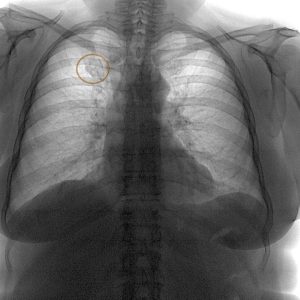

Alkalmazni kell az ellenőrzés megjelenése bármely tömítések a mellkason. Először is meg kell csinálni egy átvilágítás rosszindulatú. Másodszor, sok a betegség sürgős kezelést, így nem hoz létre semmilyen komplikáció.